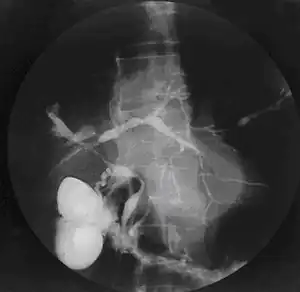

Cholangiogram of primary sclerosing cholangitis

Historically, a cholangiogram would be obtained via endoscopic retrograde cholangiopancreatography (ERCP), which typically reveals "beading" (alternating strictures and dilation) of the bile ducts inside and/or outside the liver. Currently, the preferred option for diagnostic cholangiography, given its noninvasive yet highly accurate nature, is magnetic resonance cholangiopancreatography (MRCP), a magnetic resonance imaging technique. MRCP has unique strengths, including high spatial resolution, and can even be used to visualize the biliary tract of small animal models of PSC.[19]